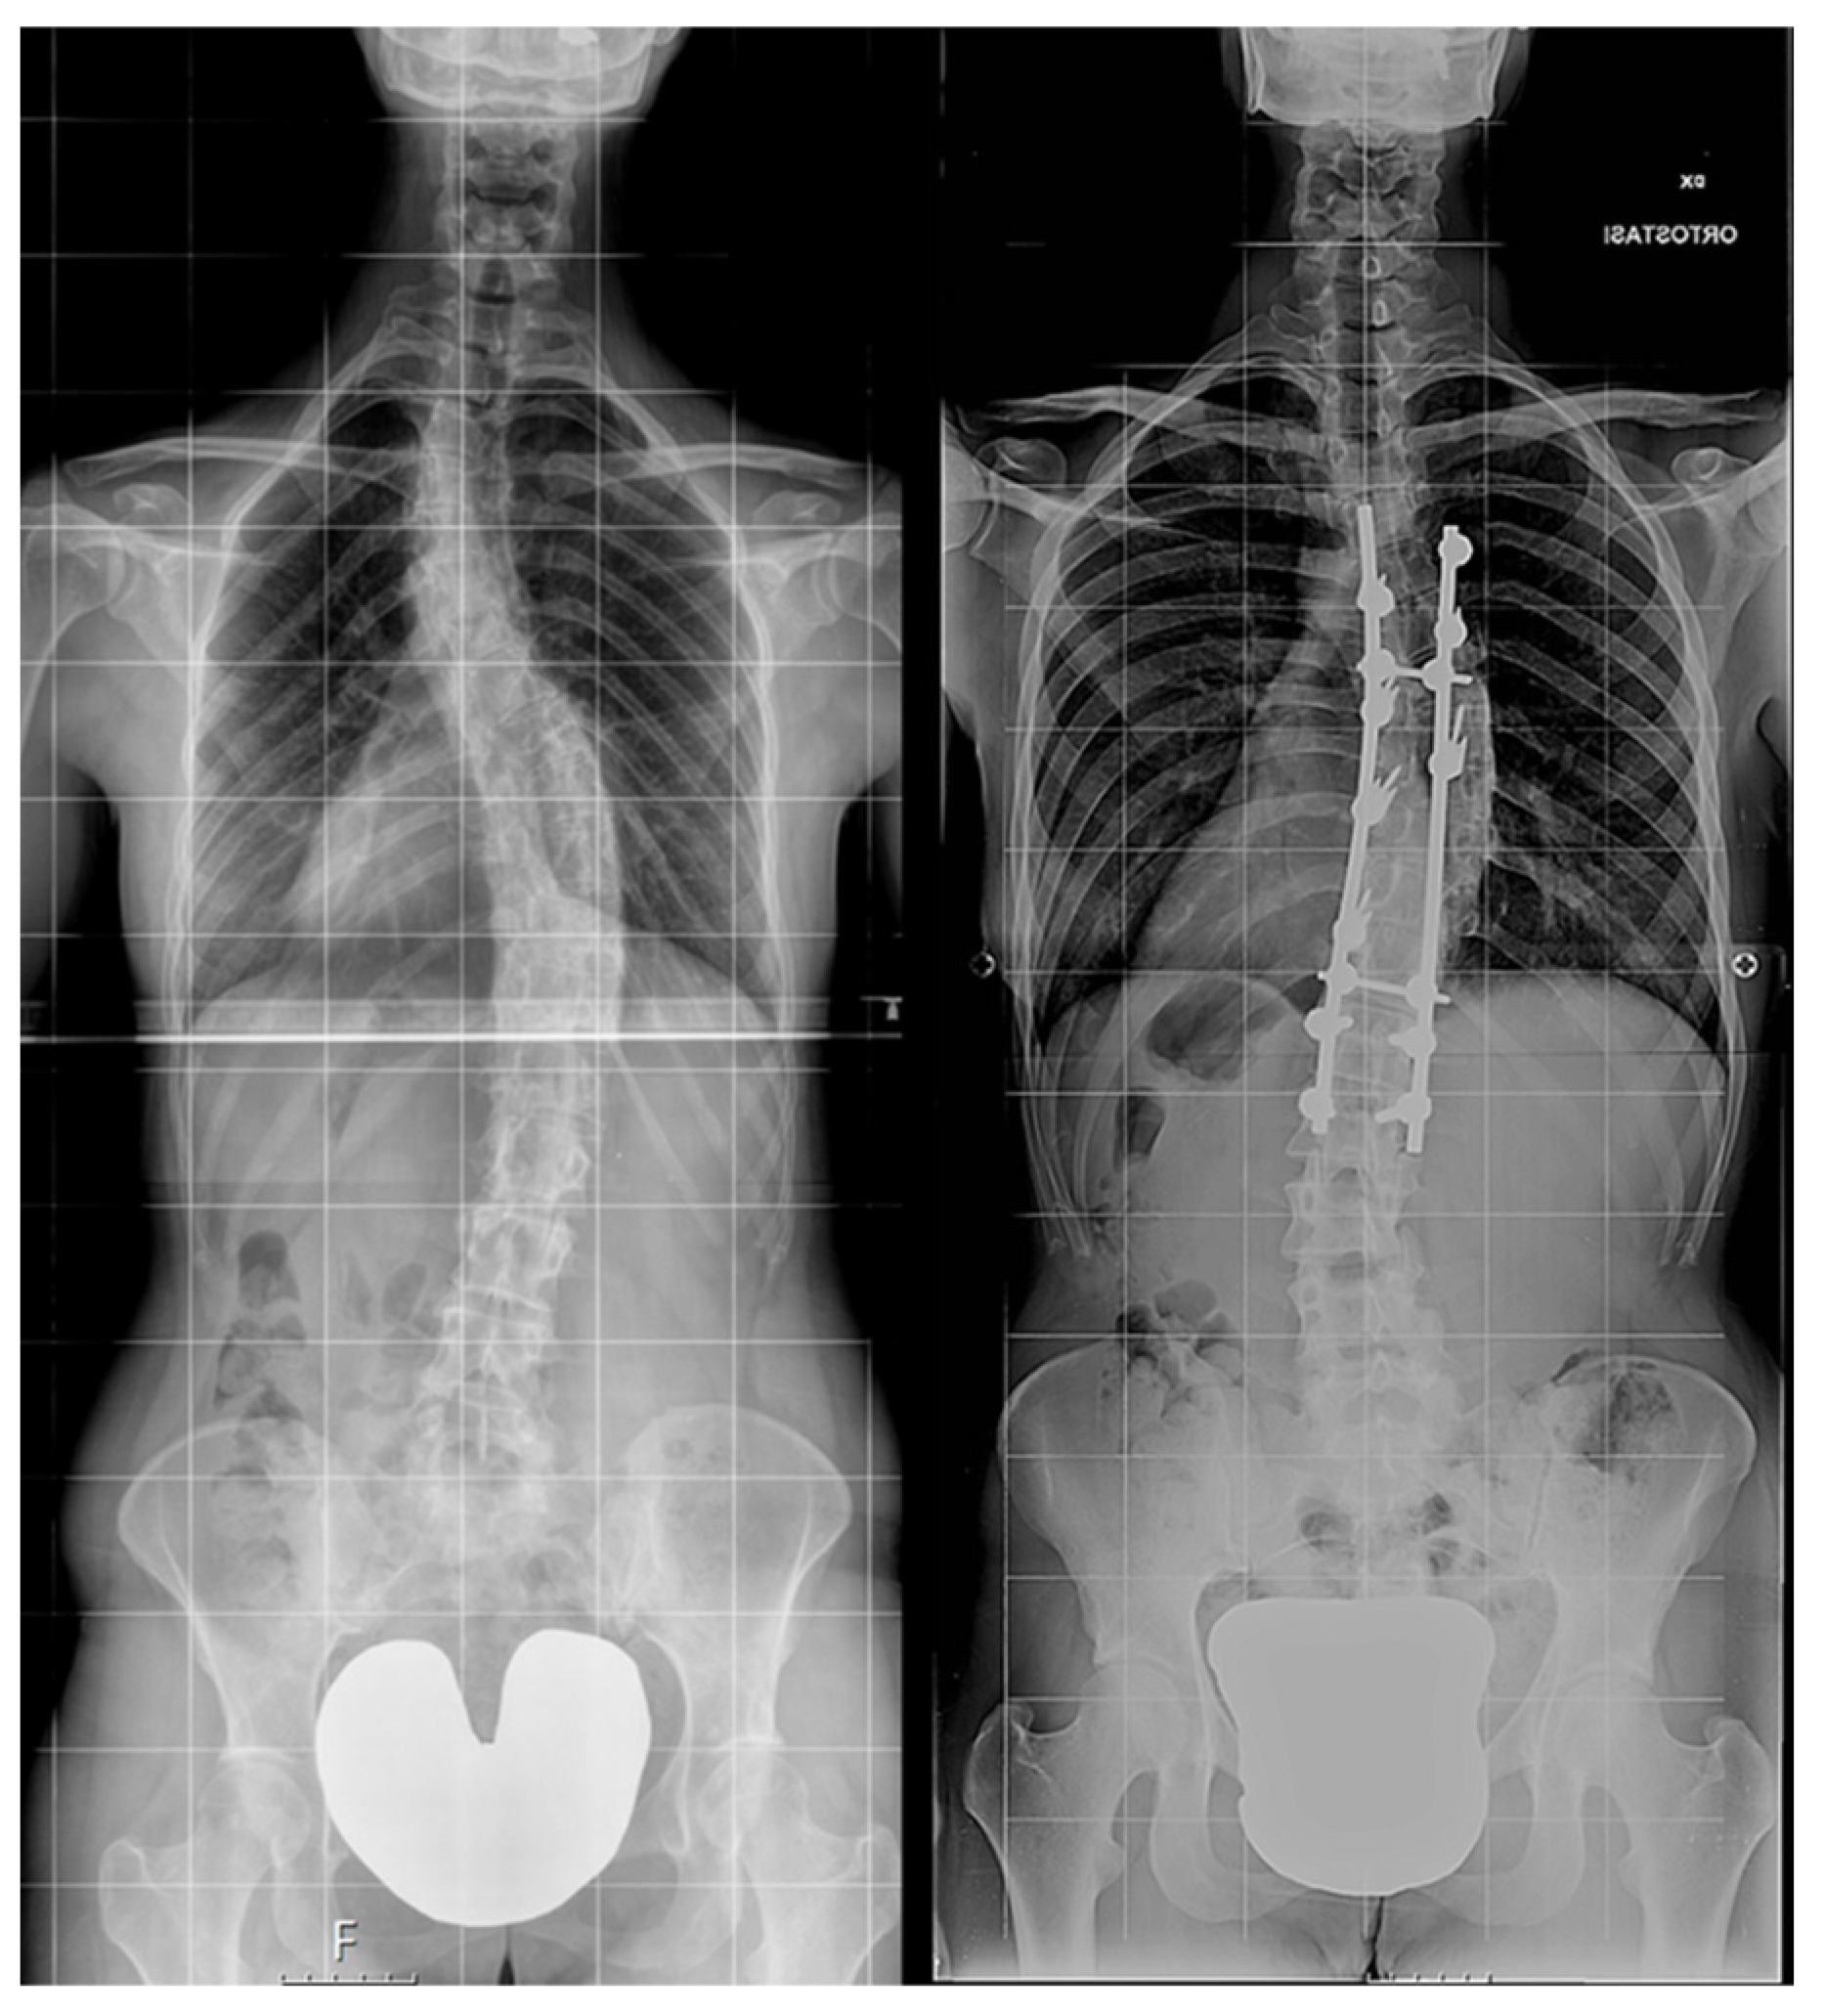

Then, patients were further subdivided into two groups depending on the surgical procedure performed (Figure 2):

Figure 2.

Examples of non-instrumented (left) and instrumented (right) long-term X-ray.